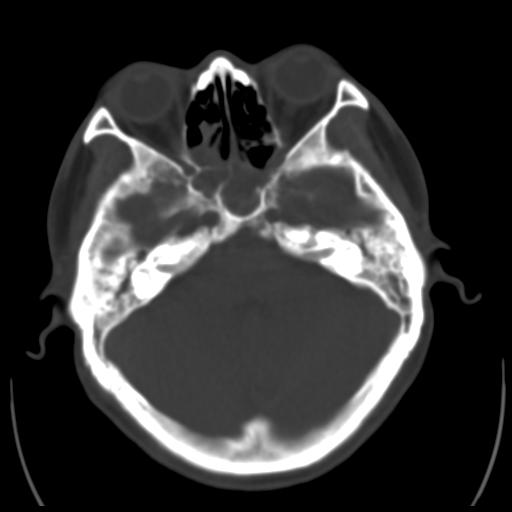

35m 鼻子时不时流血,头及右侧面部痛,颈部淋巴结未见明显大

软组织窗

考虑鼻咽癌侵犯颅底并突入右侧鼻腔;双侧中耳乳突炎。

蝶窦,后组筛窦及鼻咽部团块状软组织影,骨壁破坏,病变较广泛。考虑恶性肉芽肿。建议活检。

颅底骨质明显破坏 支持鼻咽癌 但病灶的边缘毛糙 不能除外炎性